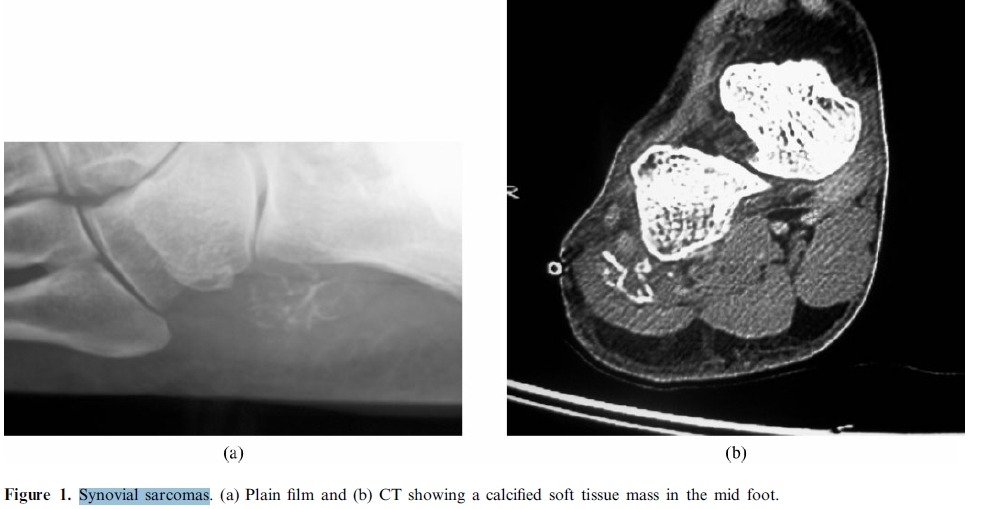

sarcoma (from the Greek sarx (σάρκα) meaning "flesh") is a cancer that arises from transformed cells of mesenchymalorigin. Thus, malignant tumors made of cancerous bonecartilagefatmusclevascular, or hematopoietic tissues are, by definition, considered sarcomas. This is in contrast to a malignant tumor originating from epithelial cells, which are termedcarcinoma. Human sarcomas are quite rare.[citation needed] Common malignancies, such as breastcolon, and lung cancer, are almost always carcinoma.